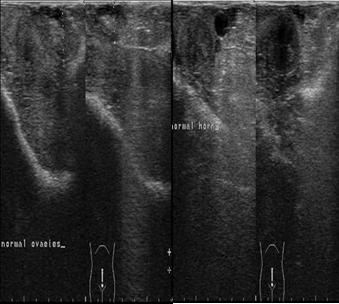

The ultrasonographic imaging of the uterus and ovaries was performed daily 9th day postpartum then followed by examination twice weekly until the 21st day postpartum. The ultrasound examination showed normal uterine involution and no abnormal secretions in the uterus (Figure 2).

Figure 2.Ultrasonographic image of ovaries (a) and uterine horn (b) at the 9th day postpartum in female camels, the image illustrate normal ovarian structure with no ovarian cysts and the uterus showed normal uterine involution and no abnormal discharges.